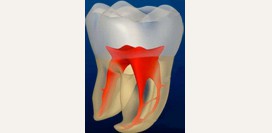

- Дентин – основное вещество, из которого образованы зубы человека. Дентин состоит на 28% из органических веществ и на 72% — из неорганических. В дентине выделяют наружный и внутренний слой. Волокна, которые входят в его состав, проходя в тангенциальном и радиальном направлении, взаимно перекрещиваются. Это придает зубу дополнительную прочность. Внутри дентин имеет полость, которая внутри корней зуба переходит в корневые каналы.

- Пульпа – совокупность мягких тканей, находящихся внутри зубной полости и корневых каналов. В пульпе проходят сосуды и нервы зуба. В области верхушки зуба имеется отверстие, через которое пульпа переходит в ткани, окружающие зуб (ткани периодонта).

- Глубокий кариес. Патологический процесс достигает пульпы.

- Пульпит. Представляет собой воспаление мягких тканей зуба – пульпы. Чаще всего развивается как острый процесс, который сопровождается острыми болями, распространяющимися на соседние зубы, челюсти.